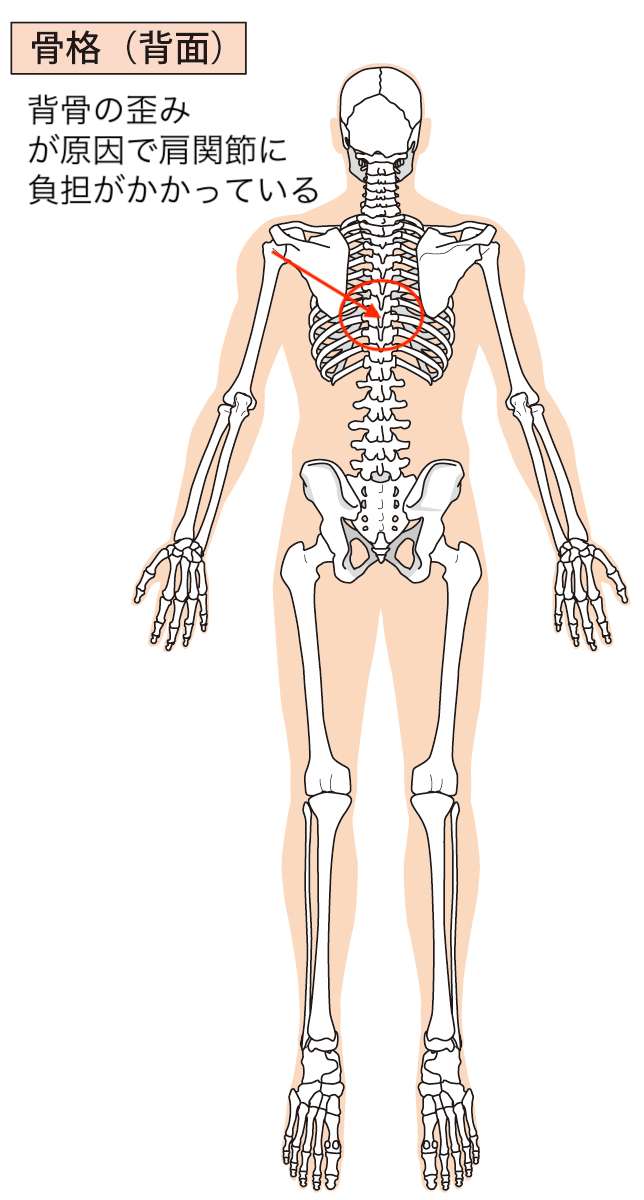

図をご覧ください。

図をご覧いただくとわかると思いますが、肩を痛めた際に背骨を歪ませた可能性があり、その背骨の歪みの影響で肩関節に負担がかかっているような状態がありました。

ここの原因が夜間痛(腕の痛み、だるさ)とも関連しているということもわかりました。